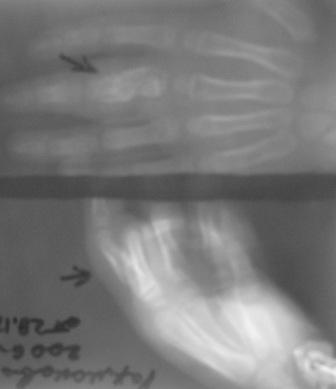

Уважаемые коллеги, на осмотре девочка 2006 г.рожд. Со слов матери 3мес. назад заметила припухлость основного фаланга 3-пальца, которая постепенно увеличилось до настоящего размера где-то в течении месяца, не болит, ребенка не беспокоит, признаки воспаления отсутствуют. Консультация онколога, биопсия - опухоль исключена (со слов матери), фтизиоортопед - тбс исключен. От основной фаланги 3 пальца к головке 4-пястной кости под кожей прощупывается хрящевидная ткань. Р-граммы от 10 декабря и 15 февраля, и фото прилагается. Что делать? Уважаемые коллеги, помогите! С уважением Абдурашид.

Конечно, мы во время операции будем брать материал на гистологию, а также удаление очага и замещение аутотрансплантатом тоже в плане рассматривается, как на примере, которая была представлена на форуме. правда снимки не очень качественные, прощу извинения!